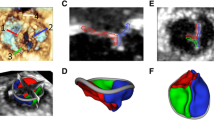

The 3D volumetric imaging data was reassembled into three 2D image planes (coronal, sagittal and axial) in which the target anatomy was identified and the segmentation region of interest was created based on the threshold intensity of pixels. It included the segmented inner region and the boundaries of the specific anatomic structures (muscle, soft tissue, blood volume or calcified structures), as shown in Figs. 2, 3 and 6. Non-cardiac anatomic data was manually eliminated (see segmentation panel in Figs. 2, 3, and Fig. 6). The valve anatomy of interest was manually identified and digitally tagged throughout the entire imaging volume then rendered into a 3D digital model (Figs. 2c, 2d, and 3). Tagged anatomic surfaces were reviewed to ensure that local structural features did not intersect or overlap inappropriately and that no contiguous surface was incomplete. The model was then saved as an STL file and exported for 3D printing.

Mitral valve reconstruction from 3D TEE images. (a) 3D TEE en-face imaging data set. (b) 2D imaging planes derived from 3D TEE data with superimposed segmentation mask over the MV leaflets. (c) Digital model of patient-specific valve. (d) Cross section of the digital valve model including the outer shell (white) and inner structure (pink). (e) En-face photo of the 3D printed patient-specific MV model. (f) Lateral view on the 3D printed MV model.

Mitral valve reconstruction from CT images. (a) CT imaging data set. (b) Identified and segmented geometry of left heart, including aortic valve, mitral valve and calcium depositions. (c) LV, Aortic and LA 3D rendered volume. (d) Lateral and en-face view on the reconstructed MV, aortic valve and calcium. (e) Apical view on MV and intraventricular structures. (f) MV integrated with left heart model. (g) En-face view on 3D printed MV model integrated in the left heart. (h) Apical view on the 3D printed multi-material model of MV and intraventricular structures.

From the volumetric imaging data, the mitral leaflets were identified, segmented and anatomically tagged using sagittal and coronal diastolic views (see Fig. 2). The mitral annulus was identified as the location where the leaflets meet the atrial and ventricular walls. The detailed geometry of the mitral apparatus was manually identified and tagged using multiple rotational views. The segmented anatomic data was rendered into a 3D digital model as shown in Fig. 3d. The pathological depositions of calcium were replicated and integrated within the posterior leaflet (yellow structure in Figs. 3d and 3e). The ventricular volume was reconstructed from the same imaging data set, along with the myocardial structure, LV outflow tract and the left atrium (LA), as shown in Fig. 3c.

Assembling models from different data sets. (a) 3D TEE data set, shown with its en-face and long-axes view. (b) Digital model of left ventricle with papillary muscles reconstructed from long-axis 3D TEE data, integrated with MV reconstructed from en-face 3D TEE data set. Apical and long-axis cross-sectional view. (c) 3D printed patient-specific model of MV within LV with papillary muscles.

Short-axis 3D TEE images of the mitral leaflets (see Fig. 2c) as well as long-axis 3D TEE images containing the LV geometry were imported into the IPS. The orientation of the MV model with the long-axis of the LV was different for each image dataset, thus requiring a manual alignment of digital MV leaflet model with the digital LV model. The mitral annulus was present in both the en-face and long-axis 3D TEE data sets and thus provided the anatomic continuity for image co-registration. The MV geometry was fused with the LV and papillary muscles into an integral digital model shown in Fig. 5b. The completed digital model was replicated into a physical 3D model (see Figs. 2e and 2f). We repeated this process using the 3D TEE data of the mitral valve leaflet geometry and annulus and fused it with the CT-derived data of the papillary muscles, chordae tendineae and LV geometry as shown in Fig. 6.

The geometries of the MV leaflets, annulus, papillary muscles and LV were successfully reconstructed from diastolic long-axis 3D TEE images (see Fig. 5b), whereas the chordae tendineae could not be accurately identified and replicated based solely on 3D TEE data. However, CT data permitted the detailed reconstruction of the subvalvular apparatus, including the chordae tendineae. To reconstruct the very fine and branched anatomy of chordae that do not appear in the single plane of CT images, it was necessary to tag the images in different views. Although the extraction of the chordae morphology was challenging, we were able to reconstruct their geometry and positions around the mitral leaflet coaptation zone. An example of the segmentation of the subvalvular anatomic data including the papillary muscles with chordae tendineae connected to the MV are shown in Fig. 6. 3D printing of the chordae tendineae has not been performed.